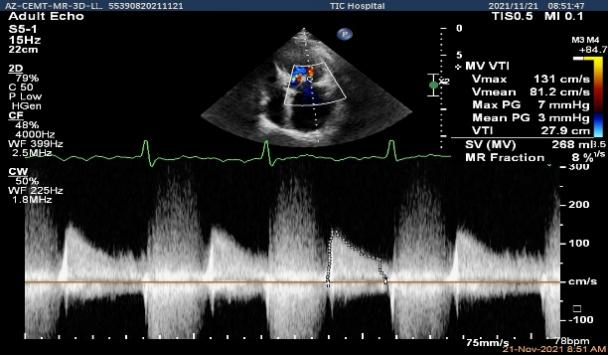

肺静脉血流频谱逐渐恢复正向,后测量平均跨瓣压差:2mmHg

二尖瓣瓣口平均跨瓣压差:3mmHg